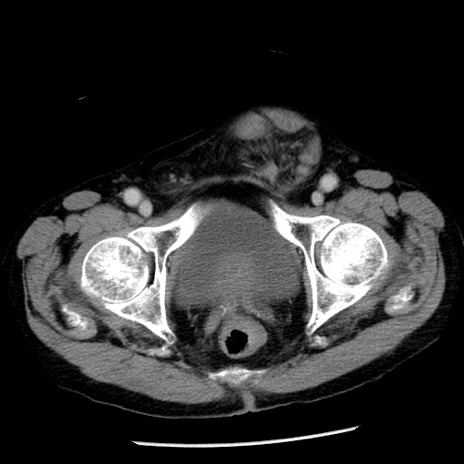

症例26(横断像)

【症例】80歳代男性

【主訴】嘔吐

【現病歴】昨晩2回嘔吐あり、今朝になっても嘔吐あり。来院。

【既往歴】胃潰瘍

【身体所見】意識清明、BT 37.6℃、BP 166/95mmHg、HR 100bpm、SpO2 97%、腹部:平坦・軟、腸蠕動音聴取良好、圧痛なし。

【データ】WBC 21900、CRP 1.46